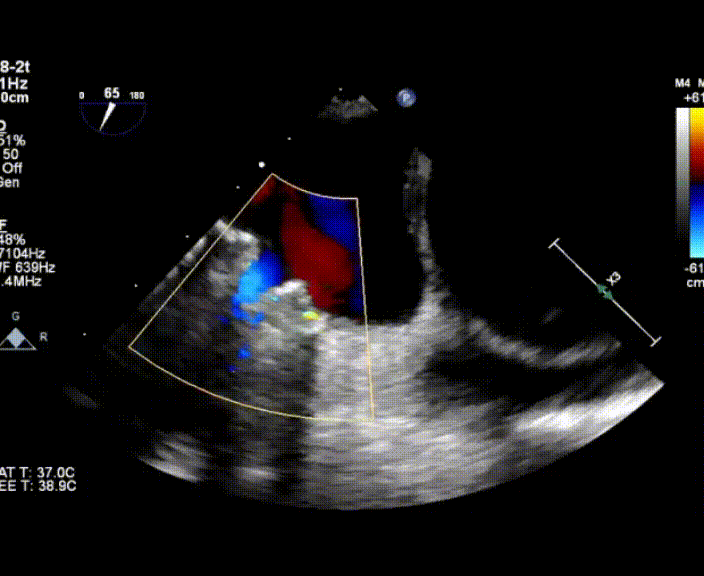

術中首先在局麻下穿刺股動脈、股靜脈,完成心導管檢查評估后轉為全麻,在食道超聲引導下穿刺房間隔,穿刺成功后將加硬導絲送入左上肺靜脈建立軌道,根據患者病情行球囊預擴張后植入6mm孔徑房間隔造孔支架,經透視及食道超聲評估支架左右盤展開良好,夾持于房間隔兩側,固定穩定、位置良好,食道彩超顯示房水平右向左為主分流,分流孔直徑符合預期大小,心導管檢查評估達到預期效果,釋放造孔支架。術后12h患者下床活動,恢復順利,擬于近日完善術后評估后出院。

心房分流術是通過器械制造穩定可控的心房間分流,適應證包括藥物治療效果不佳的左心衰或肺動脈高壓右心衰。本例患者為肺動脈高壓右心衰,術中成功放置MicroFlux®造孔支架在房間隔理想位置上,創造穩定可控的心房間分流(此例患者以右向左分流為主),在不顯著增加左心負擔的情況下,有效降低患者右心房壓力、緩解體循環淤血,增加左心輸出量,改善患者癥狀、活動耐力和生存質量。同時,國內外也已經開展多項房間隔造孔支架在射血分數保留、射血分數中間值和射血分數降低的左心衰患者中的臨床研究,結果顯示對于經過充分的規范化藥物治療后仍控制不佳的患者,心房分流術可改善患者的癥狀及生存質量。